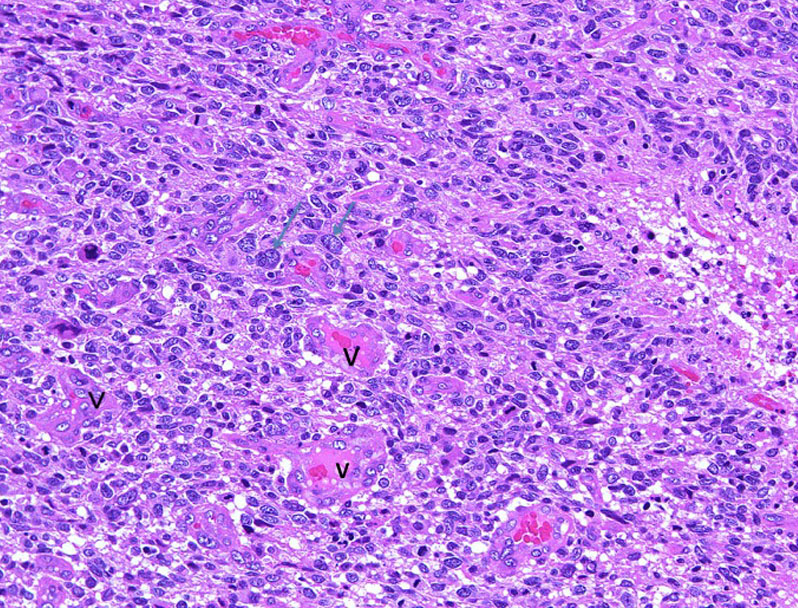

偽柵状配列の周辺部の拡大所見。chromatinに富む核の腫大と多態性(→)を示す腫瘍細胞と血管(V)の増加が見られる。

HE x200